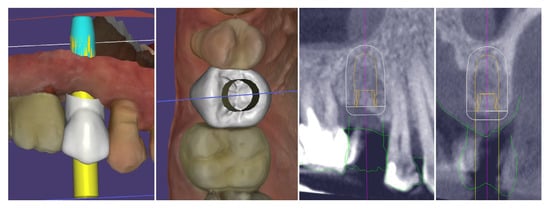

Figure 22 demonstrates the capabilities of the modern dental technology to assist the clinician in achieving accurate and reproducible results. The top row presents the congruence of the implant position with digital planning, while on the bottom row, the similarity between the prosthetic planning and the actual final crown is presented.

Figure 22.

Congruence of the implant position with digital planning and of the prosthetic planning with the final crown.